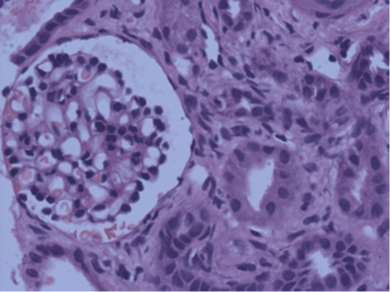

On examination he weighed 11.7 kg. He was afebrile, conscious, irritable; had peri-orbital puffiness, anasarca, B.P. 100/40mmHg, PR 130, RR 30, Saturation 99% on room air. Rest of the systemic examination was normal CNS. Venous blood gas revealed pH 7.26, pO2 30, pCO2 31.6, HCO3 13.8, sodium 117, potassium 5.7. Laboratory reports showed Hb 9, TLC 21.2, platelet 747, CRP 65, Procalcitonin 1.53, peripherial smear showed mild anisocytosis, normocytic normochromic to microcytic hypochromic leucocytosis with mild eosinophilia. BUN 54, Creatinine 7.3, sodium 126, potassium 6.5, C3 97, C4 36.8. LFT and coagulation profile values were within normal range. Urine culture, Blood cultures were negative, urine protein/creatinine ratio was 1.24, stool sample showed no growth. Chest X ray showed no signs of pleural effusion or chest infection. Patient was initiated on intravenous antibiotics piperacillin + tazobactum. On account of low urine output (10 ml), persistent hyperkalemia (6.1meq/L) and elevated s. creatinine levels (7.0 mg/dl) decision to commence with peritoneal dialysis was taken. Single cuff PD catheter was inserted under LA and peritoneal dialysis was initiated (dwell volume of 400 ml, inflow 10 min, dwell time of 30 mins, outflow 25 min). USG abdomen was suggestive of bilateral renal disease, mild ascites, right kidney 7.8cmx3.3cm, and left kidney 7.5x3.9cm. Patient underwent 5 sessions of peritoneal dialysis during his stay in the hospital. Dialysis was discontinued on 8th day of admission. His urine output gradually increased and creatinine showed declining trend. Subsequently the patient had proteinuria, hyperkalemia and the kidney function showed fluctuating creatinine levels. Patient was managed conservatively with anti-hyperkalemia medication intravenous furosemide, calcium gluconate, dextrose plus human insulin infusion and intravenous soda bicarbonate). In view of non-resolving kidney function (Creatinine 1.5mg/dl) and proteinuria (urine protein/creatinine 2.74, 24 hr Urine protein 32.9) kidney biopsy was done. Biopsy report showed that renal tubules were widely separated by interstitial edema. There was patchy acute tubular injury, interstitial edema with an associated infiltrate of lymph mononuclear cells with few admixed eosinophils. Glomerular and blood vessels are unremarkable. Based on this a diagnosis of Tubular Interstitial Nephritis was made and the child was administered intravenous methyl prednisone 250 mg in 100ml normal saline for three days followed by oral prednisone in a dose of 1mg, kg /day. Patient was discharged from the hospital with creatinine of 0.9mg/dL, BUN 28 mg/dL, sodium 135, potassium 5.3 and no protein in his urine. Post discharge on follow in OPD the patient had BUN 37, Creatinine 0.5, sodium 137, potassium 4.9, and bicarbonate 24.9. (pl add units).

Kidney biopsy report:

Acute Tubulointerstitial Nephritis

Figure 1 H&E low power view showing normal glomerulus, diffuse interstitial infiltrates, interstitial edema.